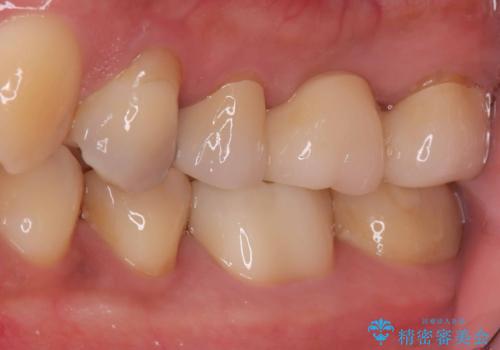

- 銀歯2本の下が虫歯になっていたので、フルジルコニアクラウンとセラミックインレーで治療を行いました。

適合が良い被せ物を入れるために、歯の境としっかり合わせた仮歯を入れ、歯茎の状態を良くしてからシリコンで型取りをしています。